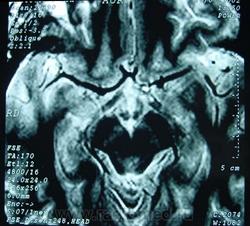

ГМ. Кавернома 2. Кавернома зрительного тракта. +

Кавернома зрительного тракта